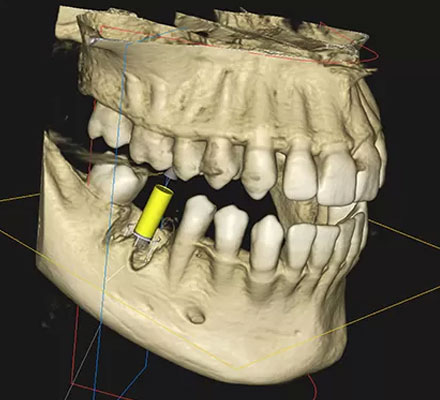

当院では、術前の診断と治療設計を最も重視し、科学的根拠に基づいた分析を行った上で、すべての工程を論理的かつ精密に進めております。また、患者様にはCT画像やシミュレーションを用いた詳細な提案資料をお渡しし、治療内容を明確にご理解頂けるよう努めております。

歯科用CTやインプラントプランニングソフトを用いて、神経や血管の位置を精密に把握し、さらにマウスピース型のサージカルガイドを作製し、安全かつ正確な埋入処置を致します。

骨の厚みや神経、血管の位置などを3次元的に解析します。